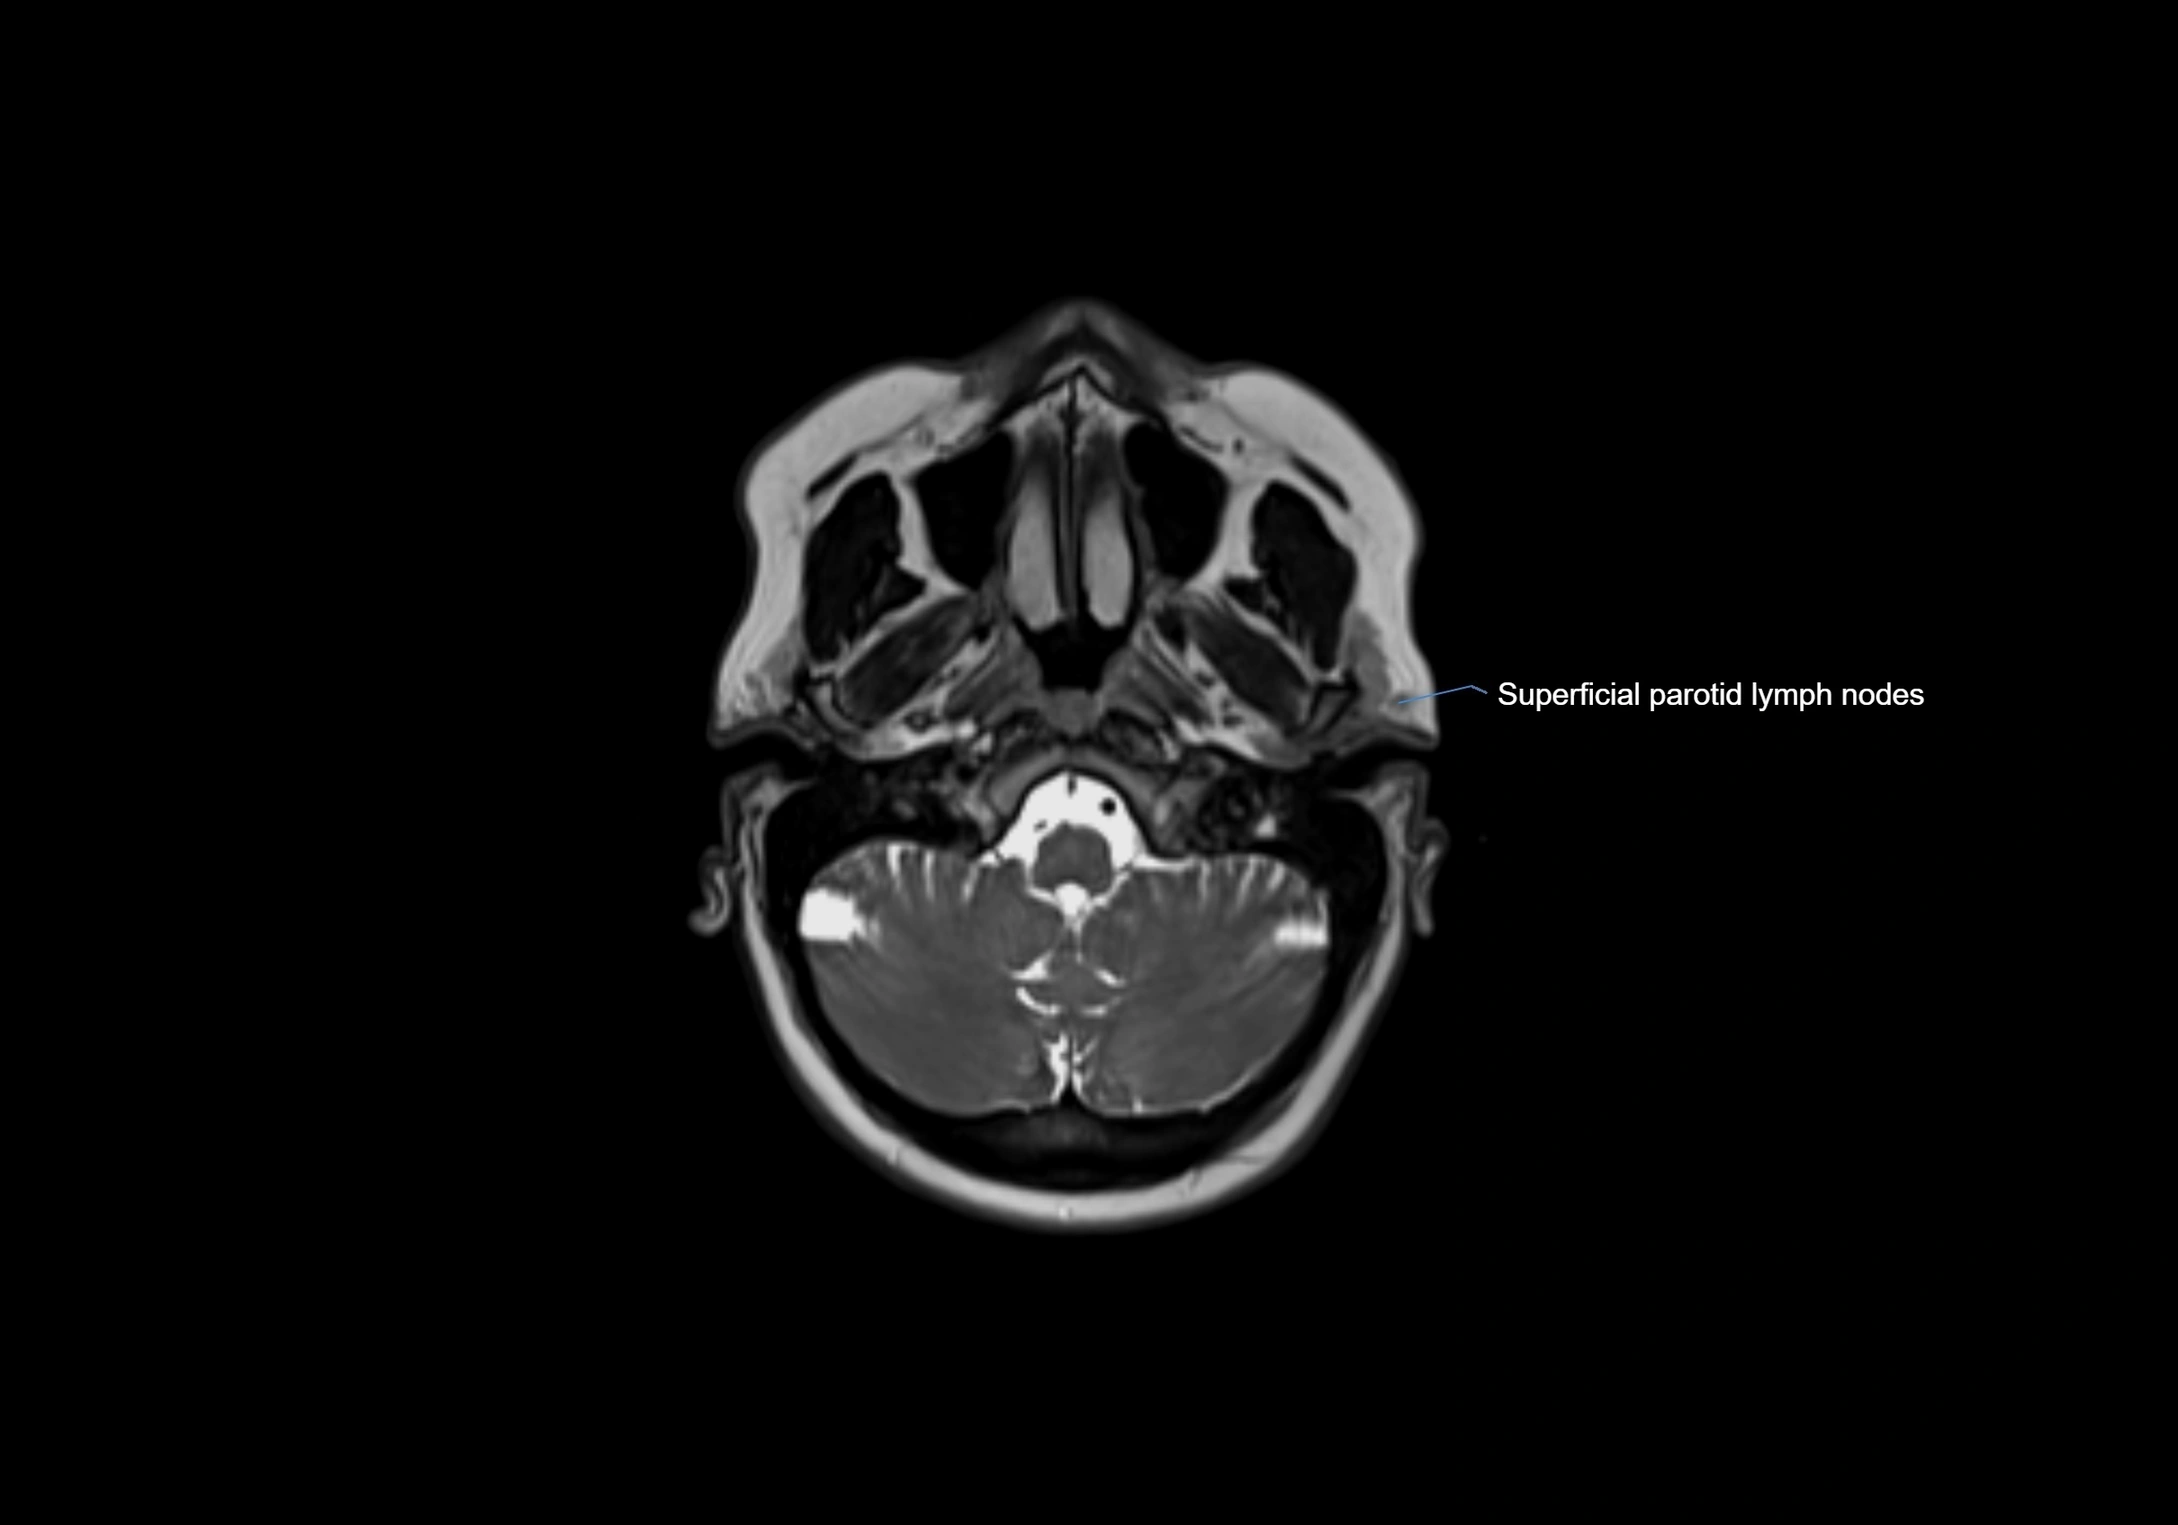

MRI Appearance

T1-weighted images:

• Normal accessory nodes appear as small, oval hypointense to intermediate signal structures within subcutaneous fat

• Surrounded by hyperintense fat, enhancing contrast for visualization

• Pathological nodes may appear enlarged or rounded, sometimes with cortical thickening

T2-weighted images:

• Nodes show intermediate signal, with surrounding fat bright

• Useful for detecting edema, inflammation, or infiltration

• Fatty hilum may appear slightly hyperintense relative to cortex

MRI images

image